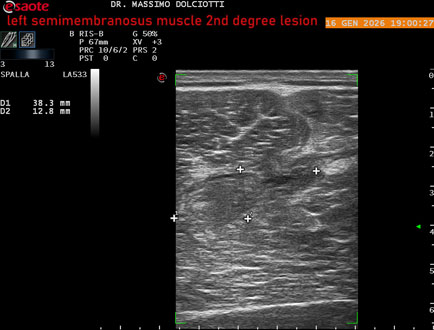

Ecografia del: 16/01/2025

Età Paziente: M 23 anni

Motivazione dell'esame: dolore coscia sinistra da tre giornii.

Commento all'esame: le immagini ed il video documentano il muscolo semimembranoso sinistro disomogeneo per area iso-ipoecogena delle dimensioni di 38 x 14,7 mm per asse corto trasversale, 81 x 22 mm per asse longitudinale, come da lesione di 2° grado, con minimo versamento siero-ematico intramuscolare.

Conclusioni: lesione di 2° grado del muscolo semimembranoso sinistro (2nd degree lesion of the left semimembranosus muscle).